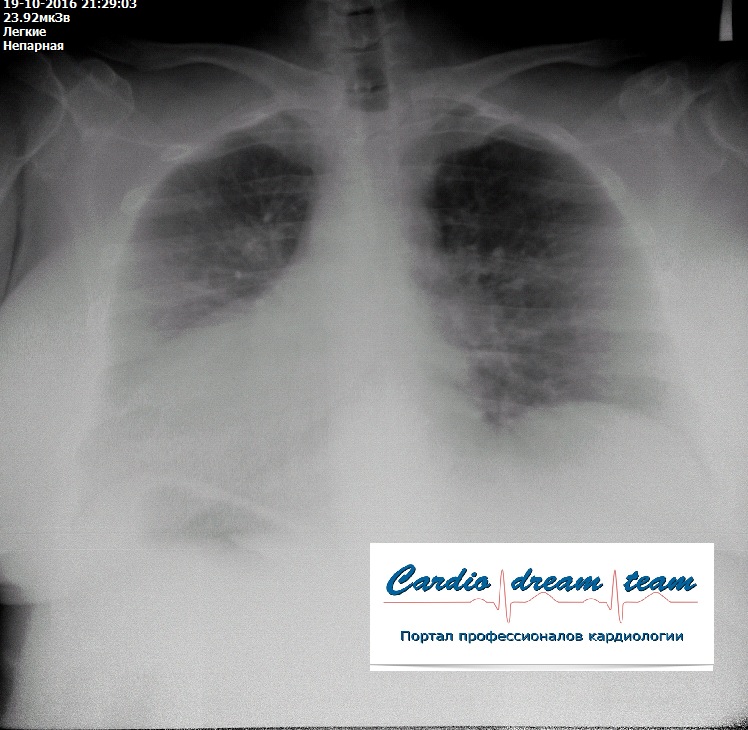

Заголовок сообщения: Артефакты на снимке

Больная согнула руку в момент съемки

Неправильное положение тела при съемке

Есть только кальцинаты, остальное кажется